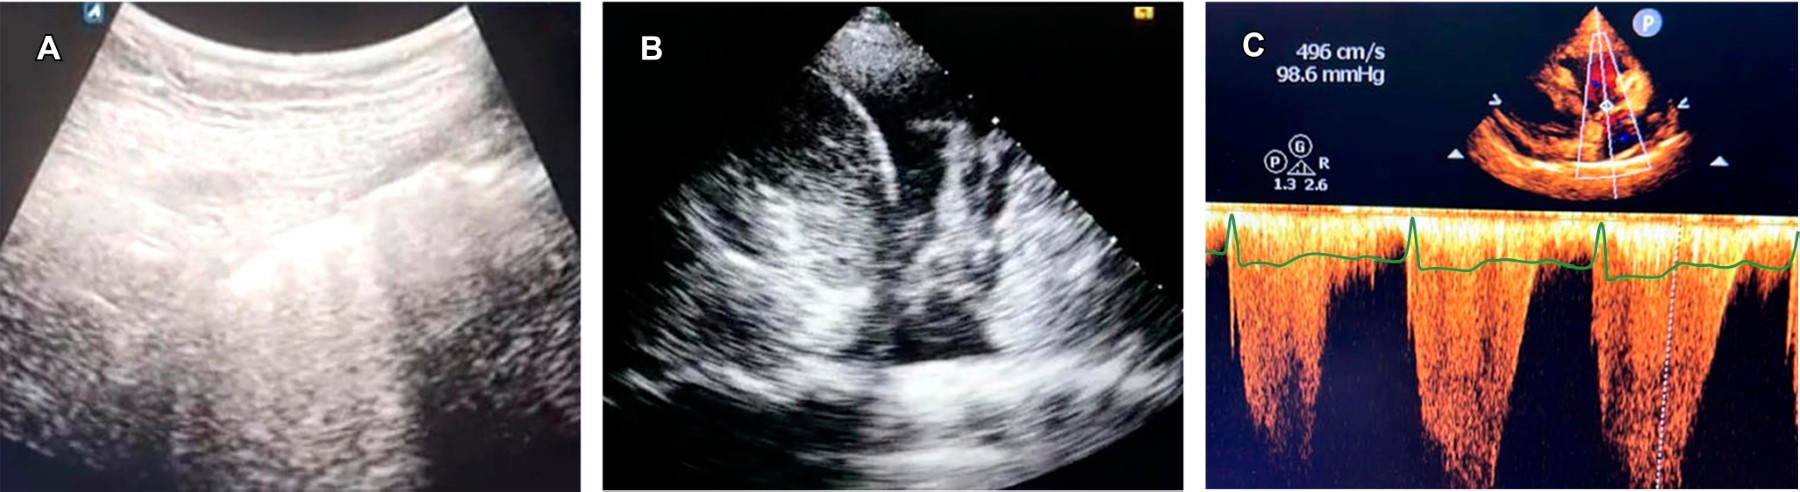

HIPERTENSIóN ARTERIAL PULMONAR

Se conoce como una enfermedad heterogénea, resultado de la remodelación patógena de las arteriolas distales pulmonares o por una vasculopatía congestiva que resulta en una hipertensión venosa pulmonar.26 Si bien, la ecocardiografía es un estudio diagnóstico a cargo de la Especialidad de Cardiología, es importante saber que es el método de elección, ya que permite estimar la presión de la arteria pulmonar y patrones de remodelado.27 Las diferencias de género se observan antes y después de los 45 años cuando las mujeres pierden el efecto cardioprotector de los estrógenos; en los hallazgos ecocardiográficos referentes al área de la aurícula derecha, predominan los valores anormales en hombres.28 La Figura 4C muestra una imagen de ecocardiograma de ventrículo derecho en un paciente con hipertensión arterial pulmonar.